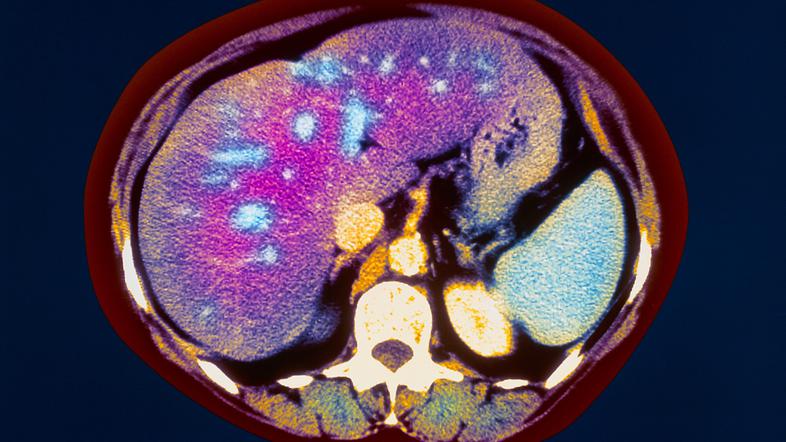

Zamaščena jetra: Težava, ki jo ima 25 odstotkov Slovencev

Praznične dietne pregrehe lahko poslabšajo tudi stanje številnih drugih bolezni, kot so sladkorna bolezen, bolezni srca in ožilja in bolezni pljuč, poleg tega lahko povzročijo zamaščenje jeter. Zamaščena jetra so bolezen, pri kateri se v jetrih nabere več maščobnih celic, kot bi jih smelo biti. Nekoč je veljalo prepričanje, da imajo zamaščena jetra zgolj tisti, ki popijejo preveč alkohola. Podrobnejše analize pa so dokazale, da alkohol ni edini povzročitelj zamaščenosti jeter. "Jetra morajo vsak dan opraviti več kot 500 funkcij v telesu, če so obremenjena z najrazličnejšimi strupi ali če so prekomerno zamaščena pa vseh teh nalog ne morejo opraviti. Na seznamu prednosti razgradnja maščob ni pri vrhu. Zamaščenost jeter sicer spodbujajo stres, vplivi iz okolja, kajenje, uživanje določenih tablet, nepravilno prehranjevanje, uživanje sladkih pijač, premalo gibanja in še bi lahko naštevali," še razloži strokovnjakinja, ki dodaja, da ima zamaščena jetra kar 25 odstotkov Slovencev.